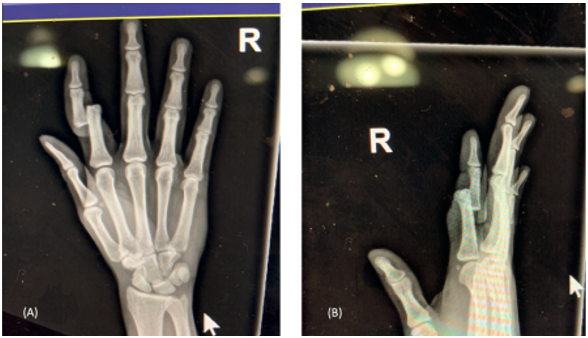

A 24-year-old male presented to the emergency department with an open, right index finger injury that occurred while playing basketball (Figure 1). Sensation and perfusion to the patient’s hand were noted to be intact. Bedside reduction under digital block was attempted without success. Given the irreducible nature of his dorsal proximal interphalangeal joint (PIPJ) dislocation, the patient was taken to the operating room for washout and reduction. A volar approach to the joint confirmed a dorsal PIPJ dislocation with disruption of the volar plate and collateral ligaments. The flexor digitorum superficialis (FDS) and flexor digitorum profundus (FDP) tendons were displaced to the radial side of the proximal phalangeal head (Figure 2). These could be seen acting as a noose on the neck of the proximal phalanx with attempted reduction. The index finger was flexed to reduce tension on the FDS and FDP tendons. The FDS was repositioned volar to the phalangeal head followed by the FDP. Gentle traction was then placed on the finger with subsequent reduction of PIPJ. Passive range of motion demonstrated a stable reduction with supporting evidence of static and live orthogonal fluoroscopic views (Figure 3). The patient was started on immediate active motion postoperatively with buddy taping of the index to the middle finger. Active motion was as tolerated with the guidance of a certified hand therapist once per week. At 3 months postoperatively, he had full flexion of the finger with a 10-degree contracture at the PIP joint. He returned to work and recreational activities with no limitations.

fluoroscopic views.